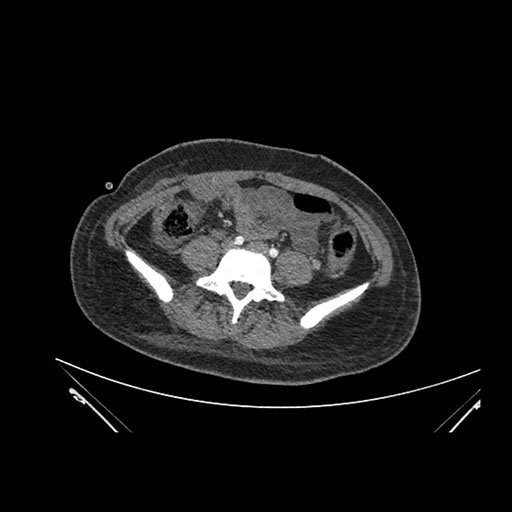

Axial Arterial

Axial Venous